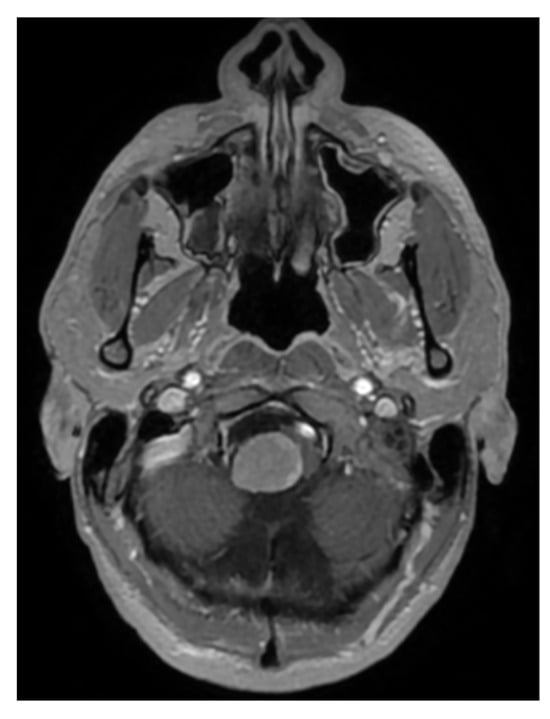

Case Report